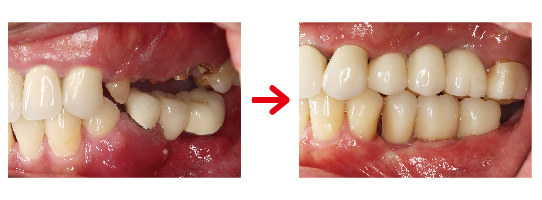

上顎區域植入了多顆植體,特別是在前牙區與後牙區的配比。

前牙區: 恢復美觀與撕裂食物的功能。

後牙區: 提供強大的咀嚼支撐力。